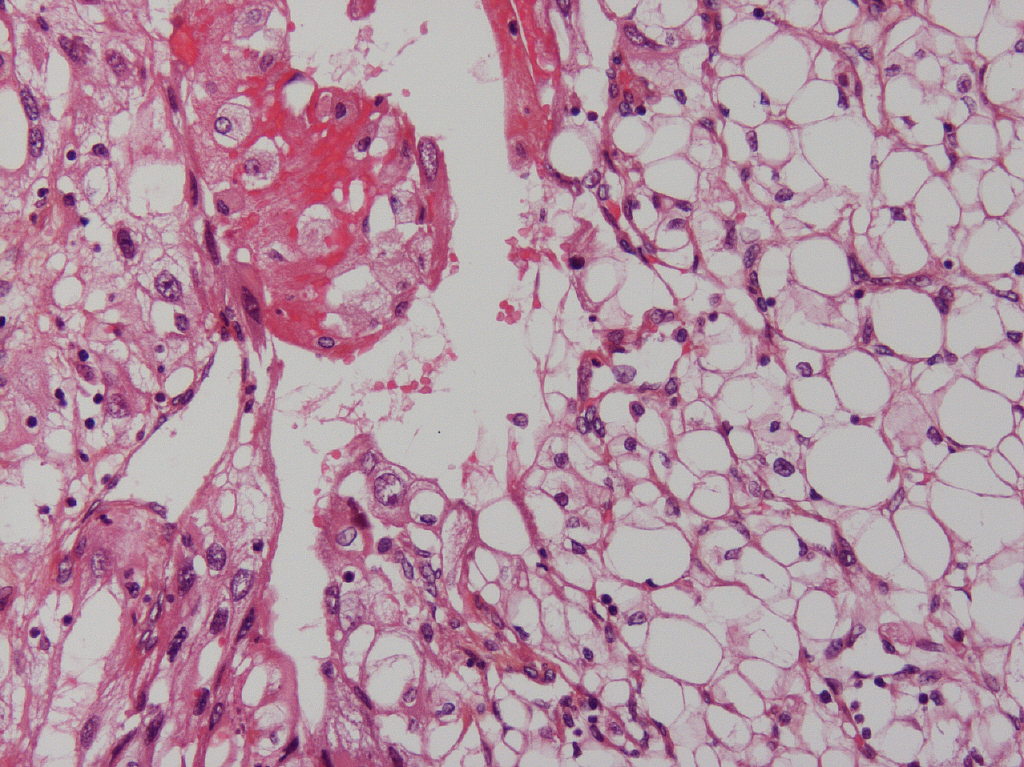

Consensus grade: WHO/ISUP grade 3

Clear cell carcinoma with different grades